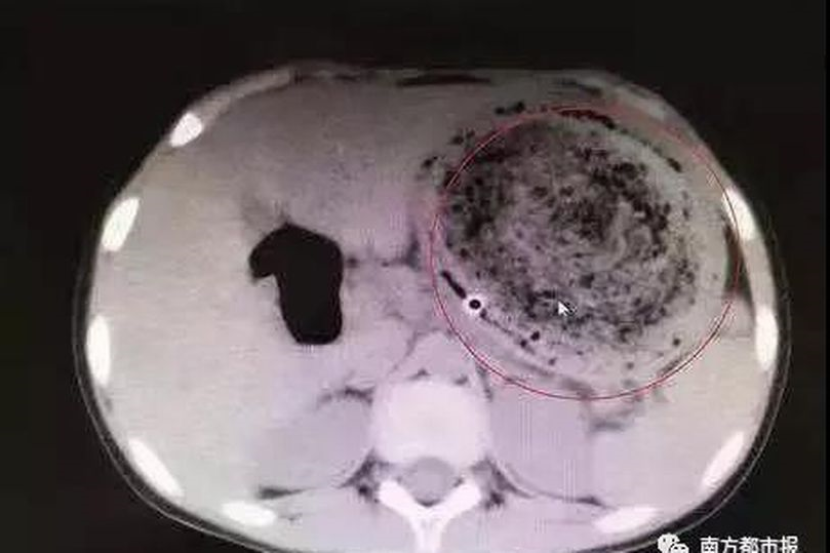

Menerusi imbasan yang dilakukan, doktor terkejut apabila segumpal rambut yang besar dikesan di dalam perutnya.

Bagaimanapun, ia tidak boleh dikeluarkan melalui endoskopi kerana ia menunjukkan tanda-tanda penyerapan.

Dr Tang terpaksa melakukan pembedahan dan mengeluarkan gumpalan rambut itu dari perut Feifei.